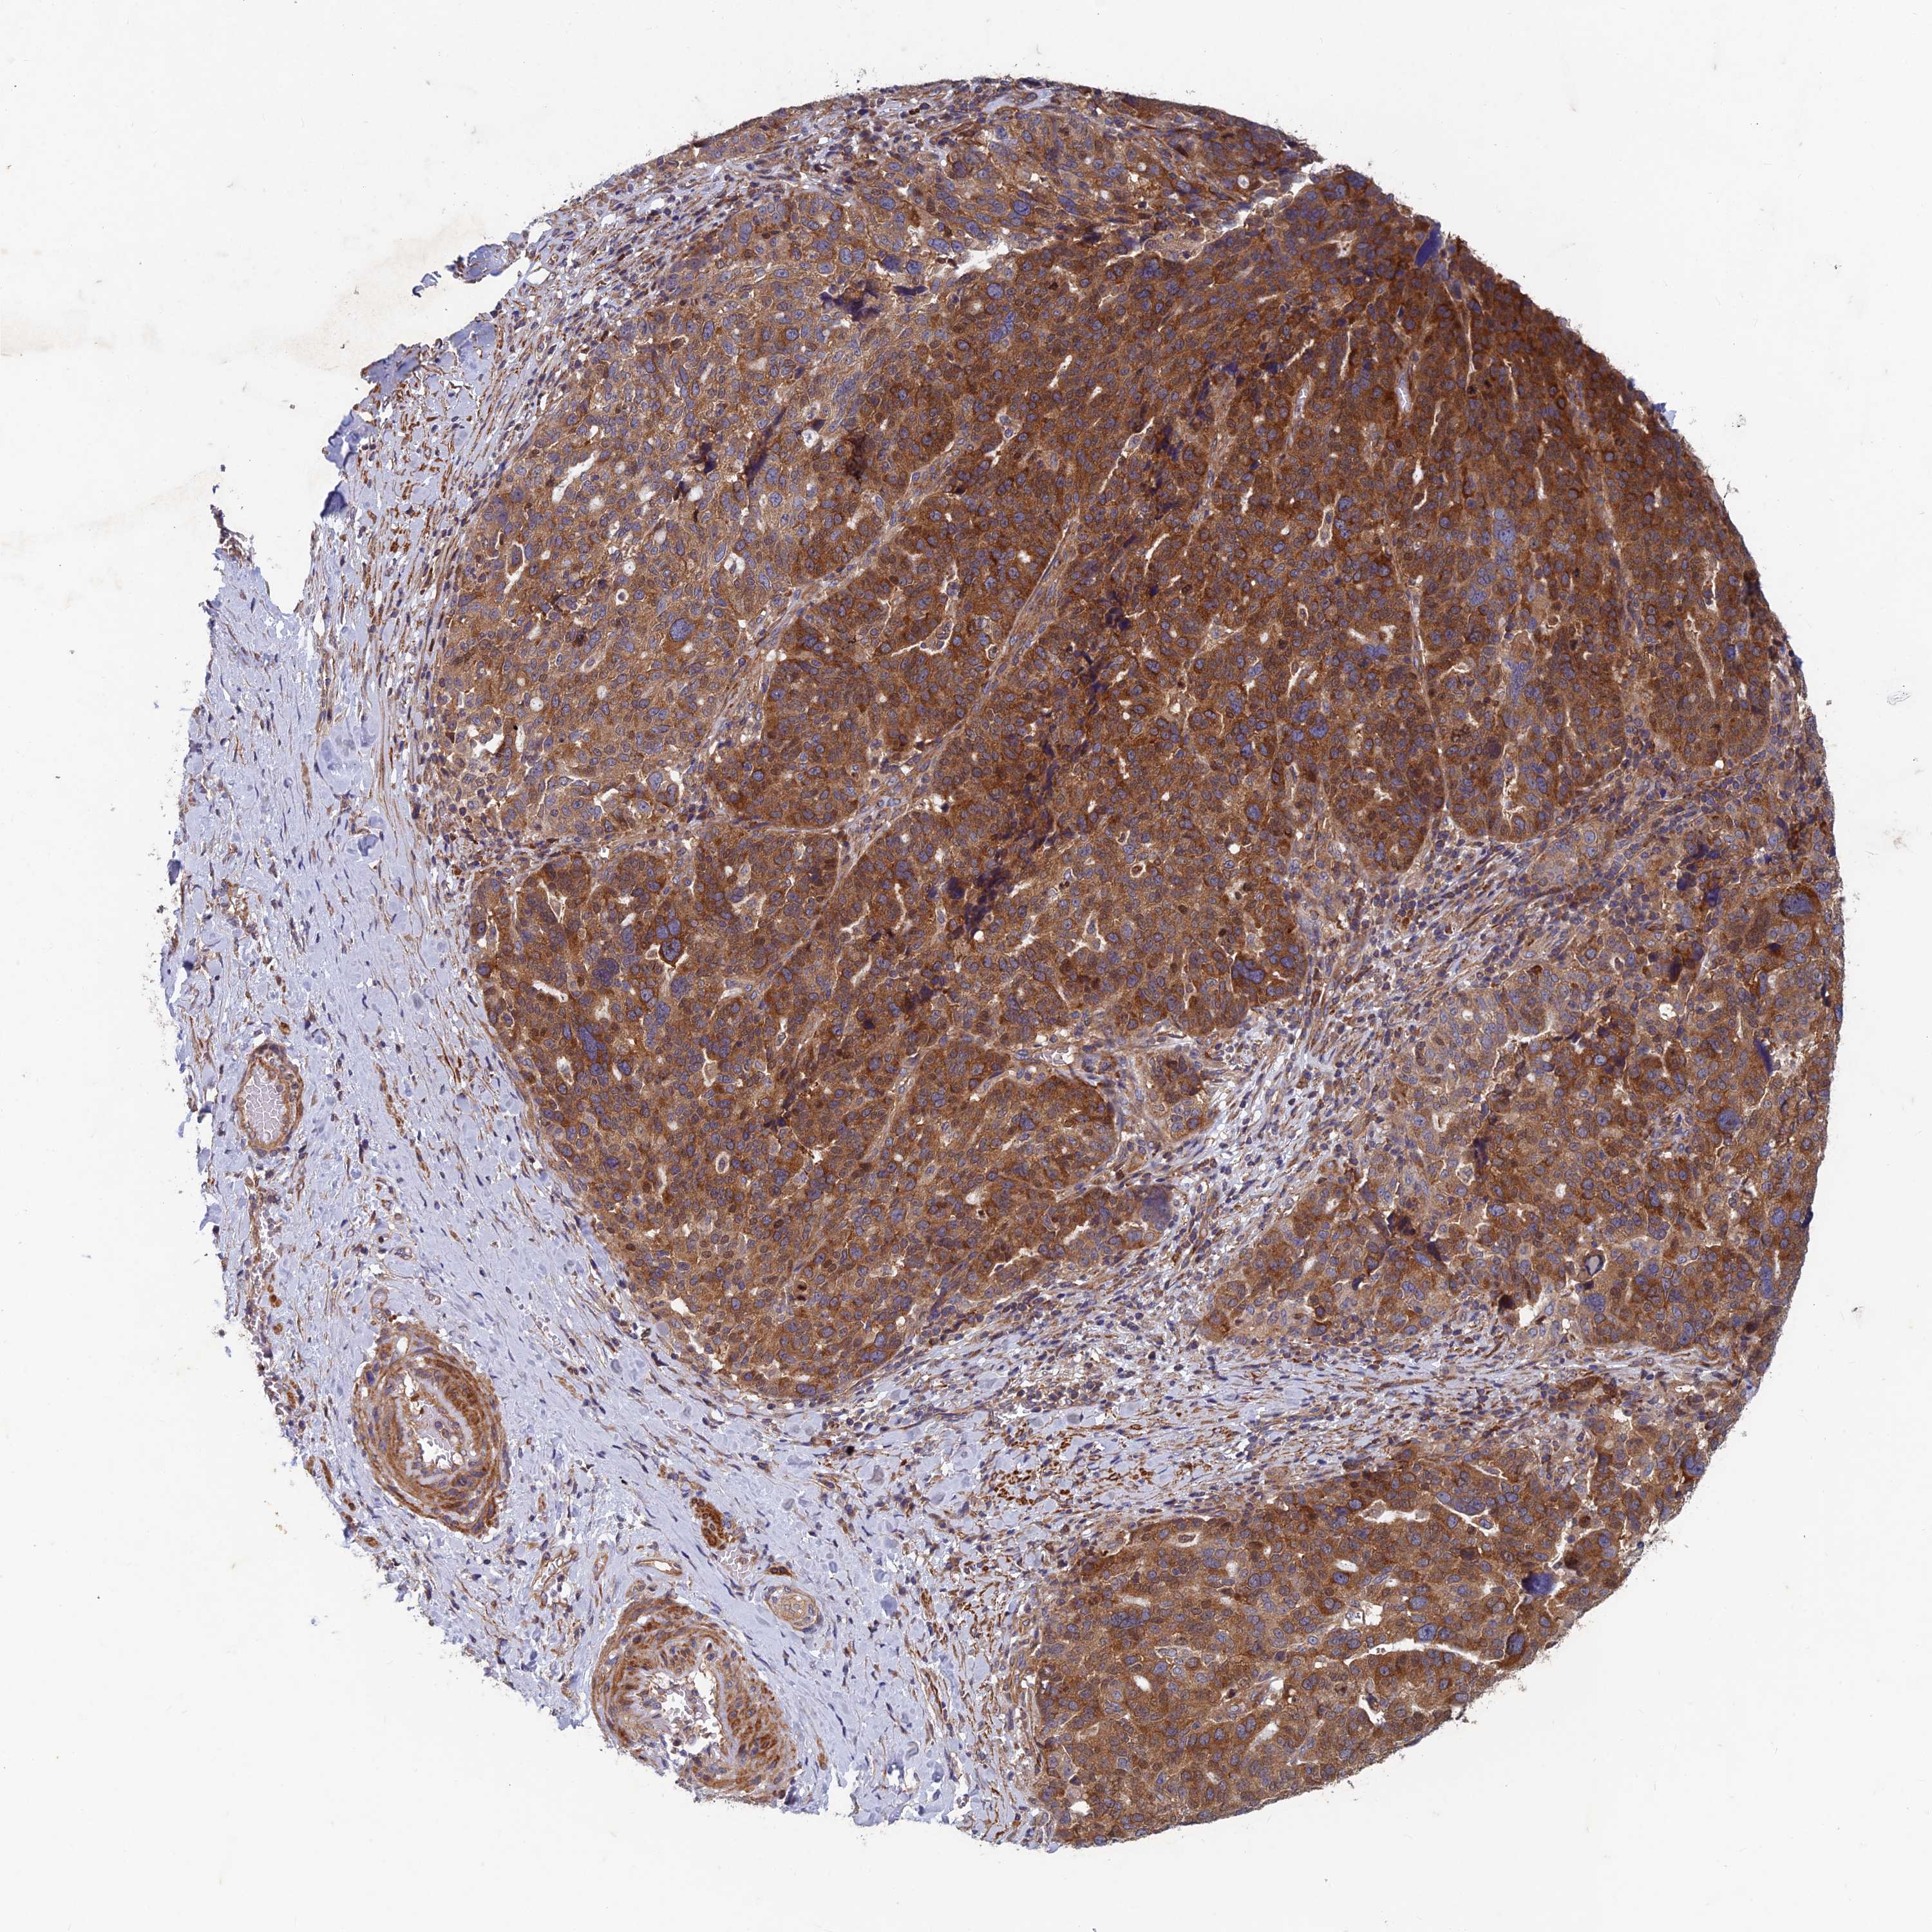

OVARIAN CANCER - Protein expressioni

A mouse-over function shows sample information and annotation data. Click on an image to view it in a full screen mode. Samples can be filtered based on level of antibody staining by selecting one or several of the following categories: high, medium, low and not detected. The assay and annotation is described here.

Note that samples used for immunohistochemistry by the Human Protein Atlas do not correspond to samples in the TCGA dataset.

Antibody stainingi

Antibody staining in the annotated cell types in the current human tissue is reported as not detected, low, medium, or high, based on conventional immunohistochemistry profiling in selected tissues. This score is based on the combination of the staining intensity and fraction of stained cells.

Each image is clickable and will lead to virtual microscopy that enables deeper exploration of all samples and also displays staining intensity scores, fraction scores and subcellular localization as well as patient and tissue information for each sample.

Antibody HPA039613

Staining

High

Medium

Low

Not detected

Intensity

Strong

Moderate

Weak

Negative

Quantity

>75%

75%-25%

<25%

None

Location

Nuclear

Cytoplasmic/membranous

Cytoplasmic/membranous,nuclear

Cystadenocarcinoma, serous, NOS

Carcinoma, endometroid

Cystadenocarcinoma, mucinous, NOS

Carcinoma, NOS